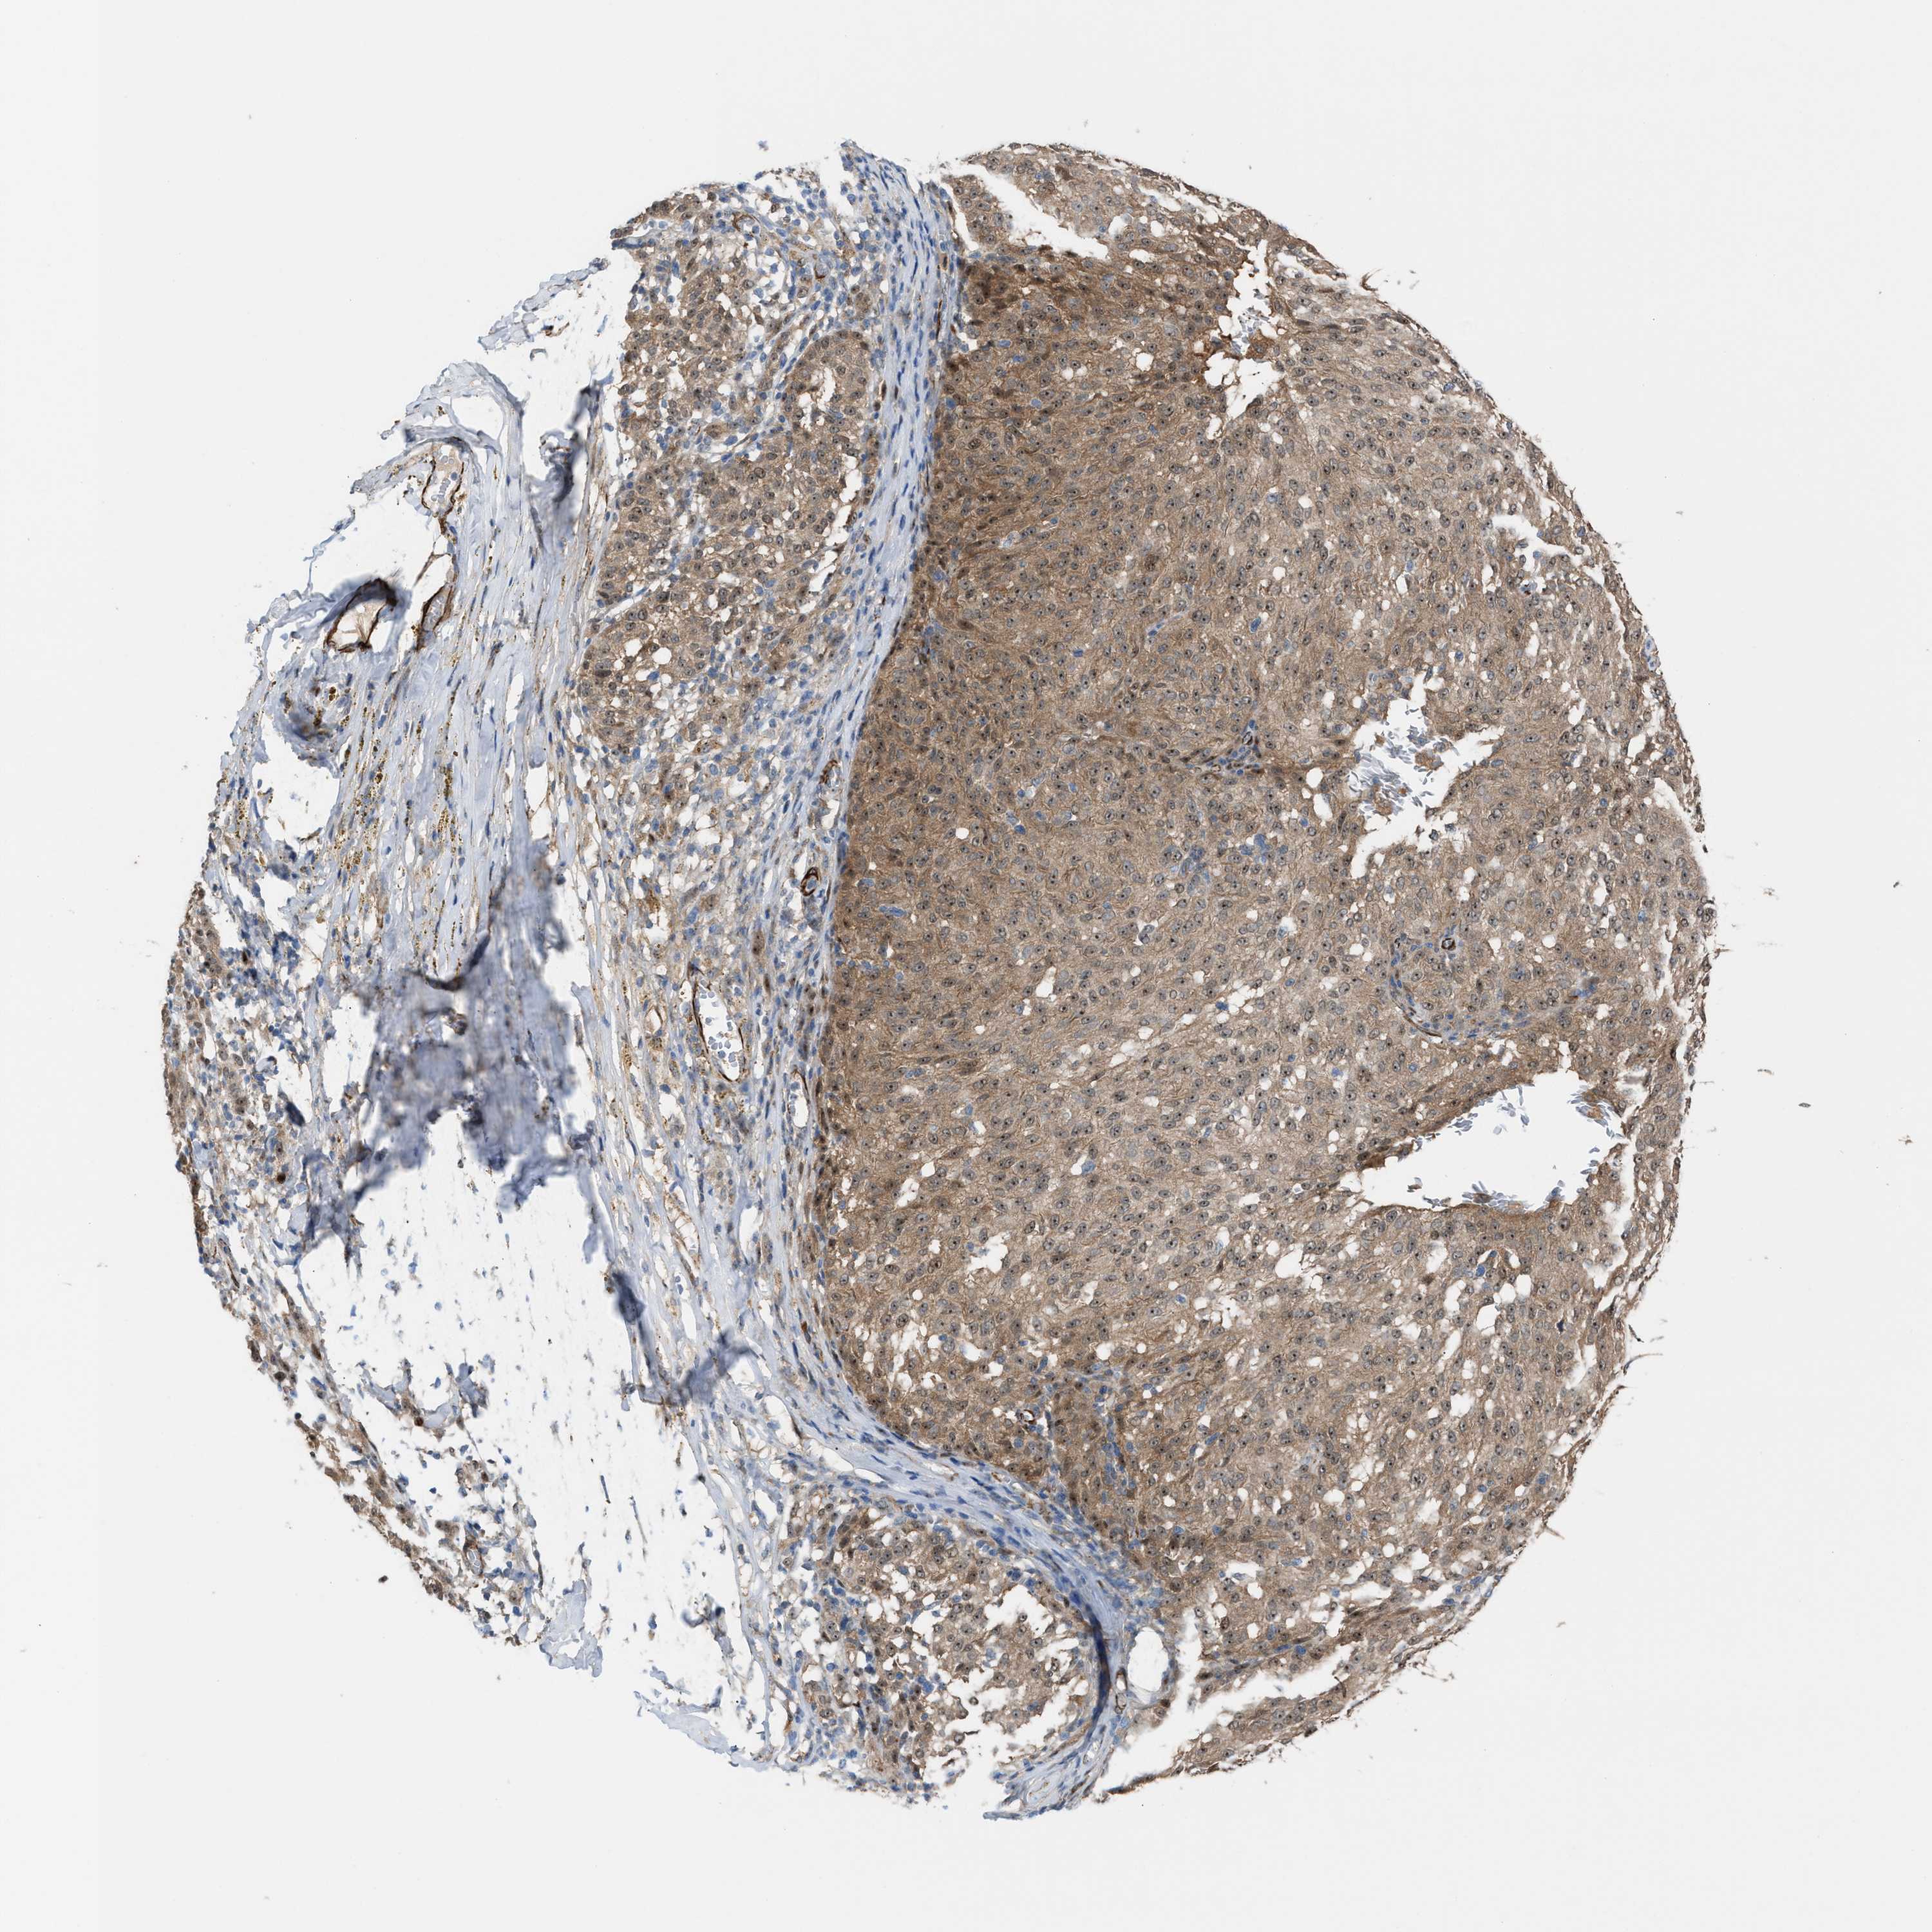

MELANOMA - Protein expressioni

A mouse-over function shows sample information and annotation data. Click on an image to view it in a full screen mode. Samples can be filtered based on level of antibody staining by selecting one or several of the following categories: high, medium, low and not detected. The assay and annotation is described here.

Note that samples used for immunohistochemistry by the Human Protein Atlas do not correspond to samples in the TCGA dataset.

Antibody stainingi

Antibody staining in the annotated cell types in the current human tissue is reported as not detected, low, medium, or high, based on conventional immunohistochemistry profiling in selected tissues. This score is based on the combination of the staining intensity and fraction of stained cells.

Each image is clickable and will lead to virtual microscopy that enables deeper exploration of all samples and also displays staining intensity scores, fraction scores and subcellular localization as well as patient and tissue information for each sample.

Antibody HPA021283

Antibody HPA021332

Staining

High

Medium

Low

Not detected

Intensity

Strong

Moderate

Weak

Negative

Quantity

>75%

75%-25%

<25%

None

Location

Nuclear

Cytoplasmic/membranous

Cytoplasmic/membranous,nuclear

Malignant melanoma, NOS

Malignant melanoma, Metastatic site